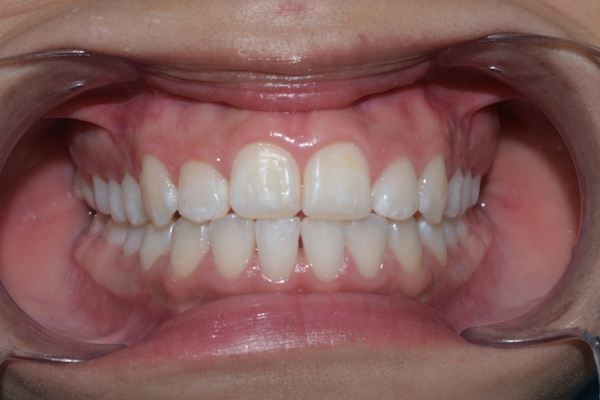

La paciente, muy contenta con el resultado final

La ortodoncia no solo mejora la apariencia, también:

- Corrige la mordida, mejorando la masticación

- Previene desgaste irregular

- Mejora la salud periodontal y reduce el riesgo de caries

- Aumenta la confianza al sonreír